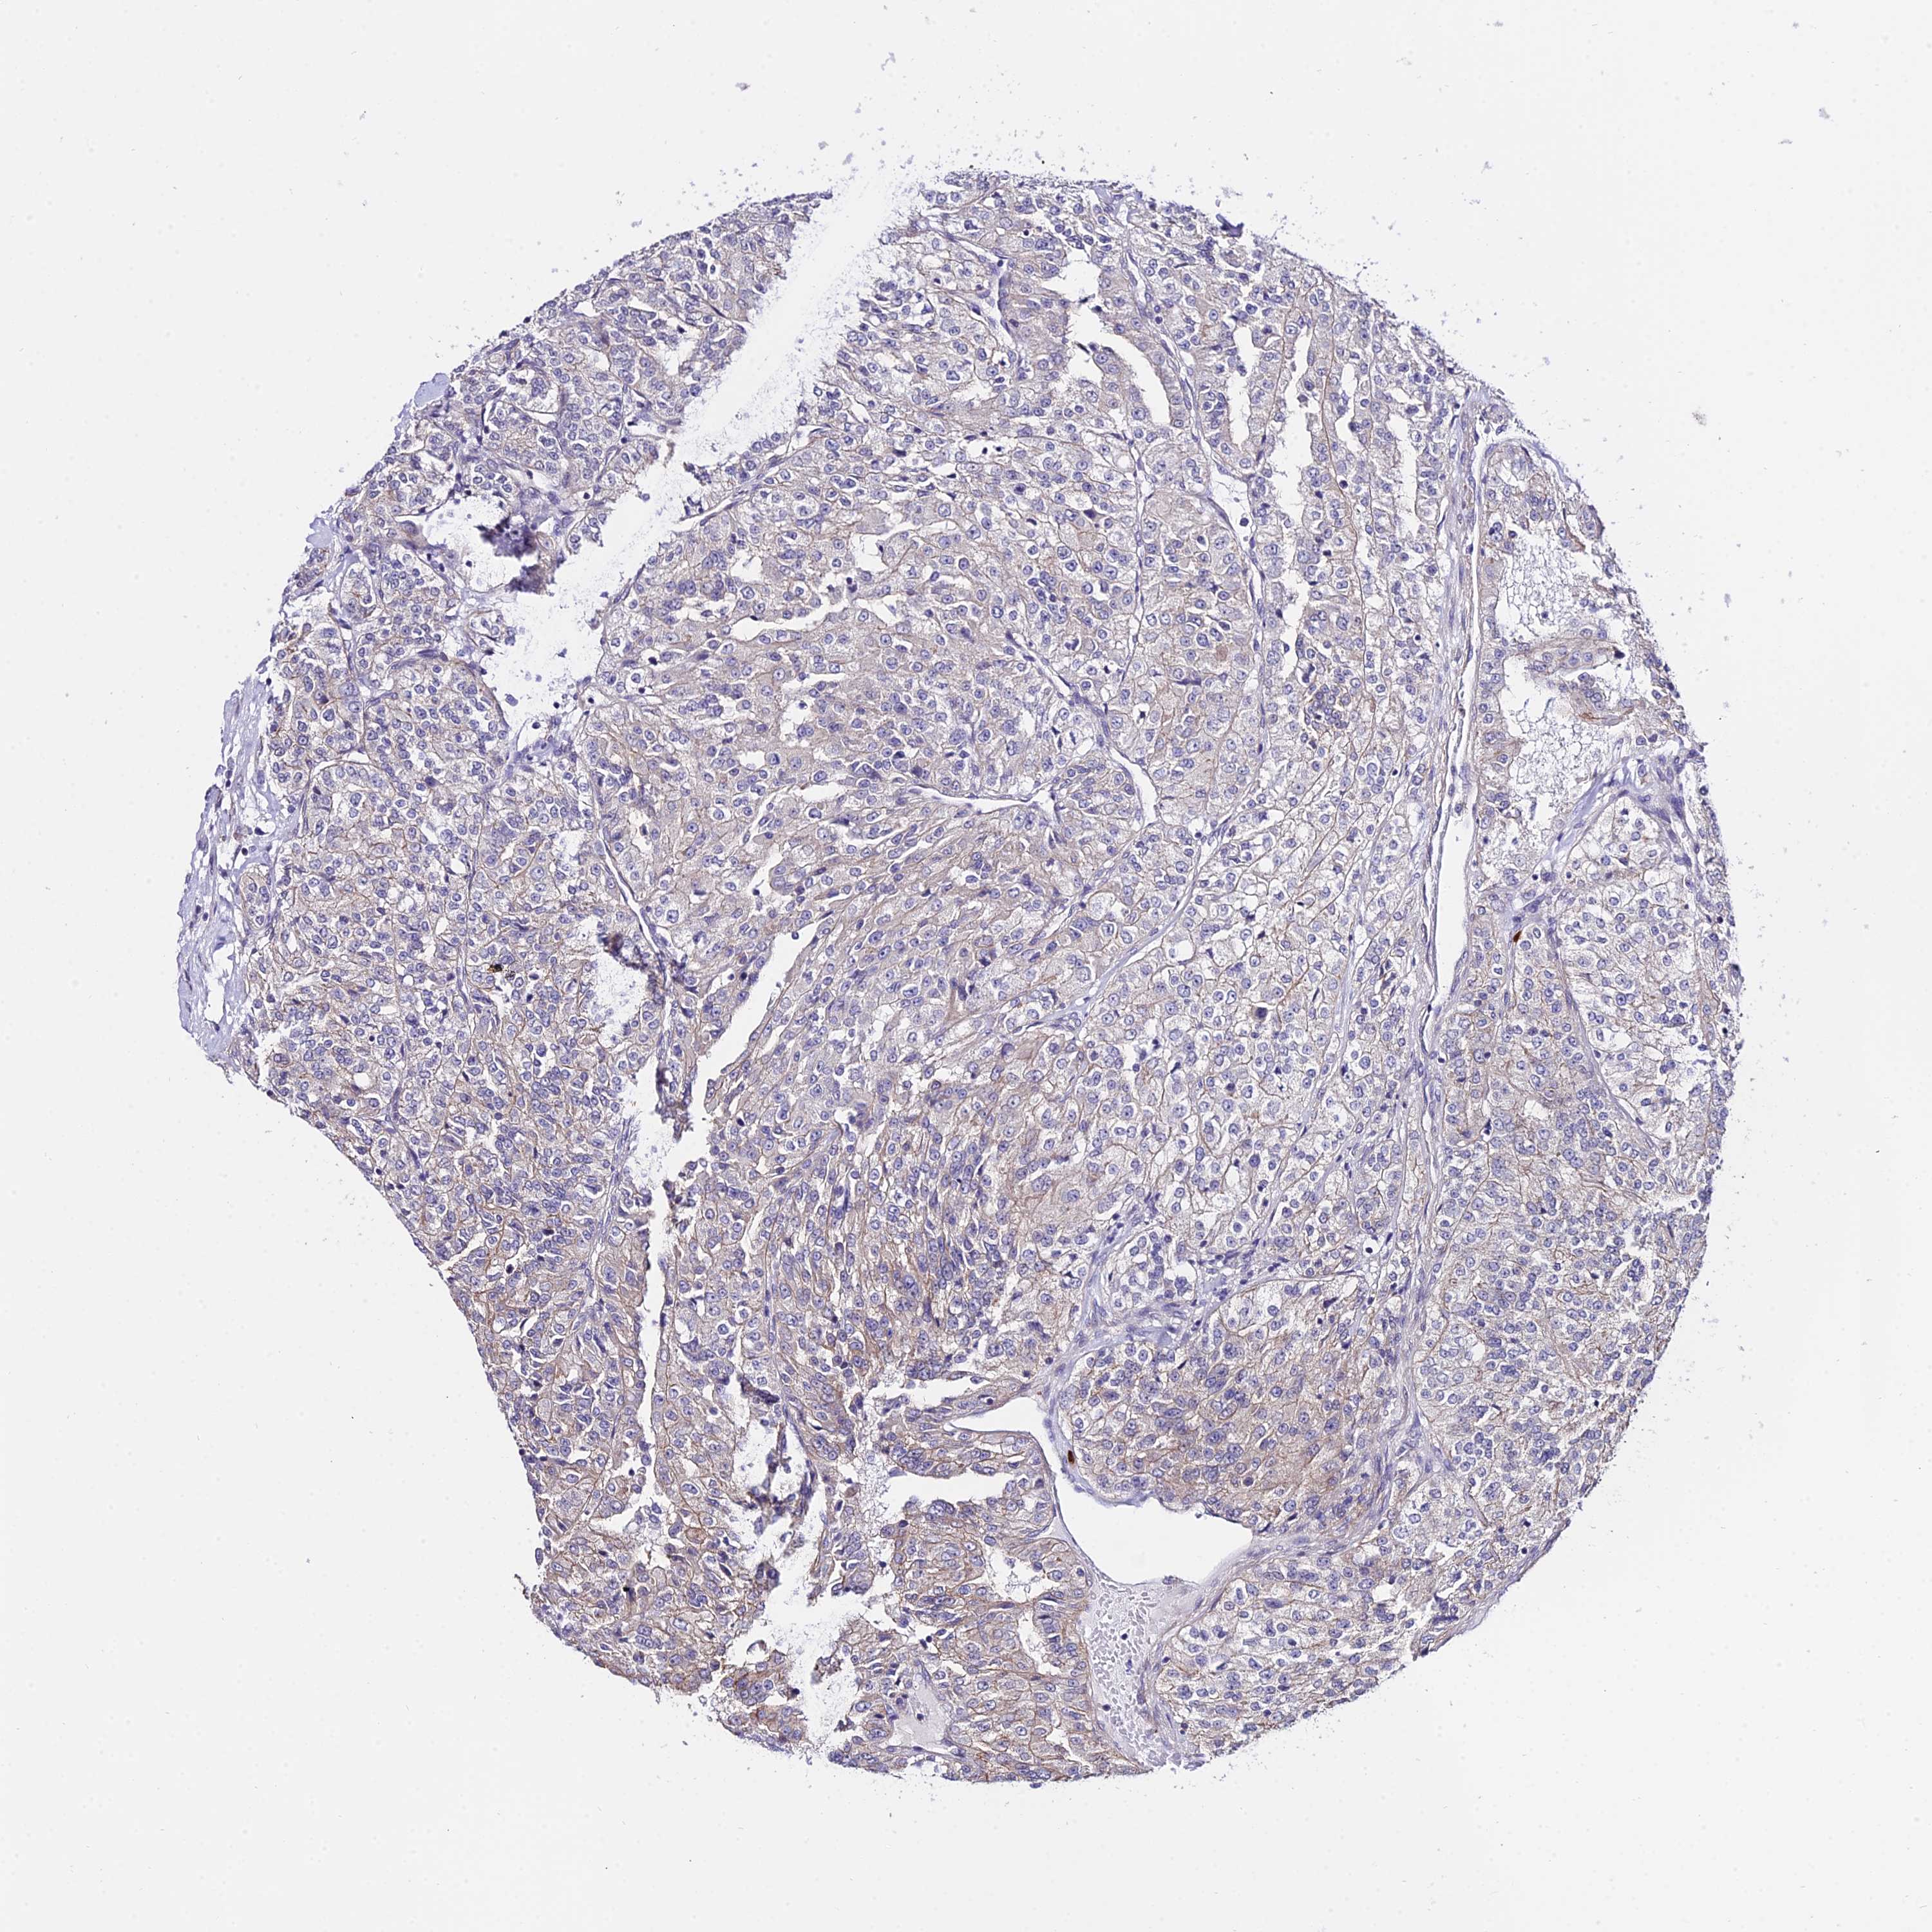

KIDNEY RENAL CLEAR CELL CARCINOMA (TCGA) - Interactive survival scatter ploti

The Survival Scatter plot shows the clinical status (i.e. dead or alive) for all individuals in the patient cohort, based on the same data that underlies the corresponding Kaplan-Meier plots. Patients that are alive at last time for follow-up are shown in blue and patients who have died during the study are shown in red.

The x-axis shows the expression levels (FPKM) of the investigated gene in the tumor tissue at the time of diagnosis. The y-axis shows the follow-up time after diagnosis (years). Both axes are complimented with kernel density curves demonstrating the data density over the axes. The top density plot shows the expression levels (FPKM) distribution among dead (red) and alive patients (blue). The right density plot shows the data density of the survived years of dead patients with high and low expression levels respectively, stratified using the cutoff indicated by the vertical dashed line through the Survival Scatter plot. This cutoff is automatically defined based on the FPKM cutoff that minimizes the p-score. The cutoff can be changed by dragging the vertical line or by entering a cutoff value in the square labeled "Current cut-off".

Under the Survival Scatter plot the p-score landscape (black curve; left axis) is shown together with dead median separation (red curve; right axis). Dead median separation is the difference in median mRNA expression between patients who have died with high and low expression, respectively. It is calculated as follows: median FPKM expression of dead patients with high expression - median FPKM expression of dead patients with low expression. This is intended to aid the user in visually exploring custom cutoffs and the associated p-scores and dead median separation.

Individual patient data is displayed and can be filtered by clicking on one or more of the category buttons on the top of the page. Categories describing expression level and patient information include: high, low, alive, dead, female, male and tumor stages. The scale of the x-axis can be toggled between linear and log-scale by clicking on the "x log" button. Mouse-over function shows TCGA ID, patient information and mRNA expression (FPKM) for each patient.

& Survival analysisi

Kaplan-Meier plots summarize results from analysis of correlation between mRNA expression level and patient survival. Patients were divided based on level of expression into one of the two groups "low" (under cut off) or "high" (over cut off). X-axis shows time for survival (years) and y-axis shows the probability of survival, where 1.0 corresponds to 100 percent.

POLR2I is not prognostic in Kidney Renal Clear Cell Carcinoma (TCGA)

Best expression cut offi

Based on the FPKM value of each gene, patients were classified into two groups and association between prognosis (survival) and gene expression (FPKM) was examined. The best expression cut-off refers the FPKM value that yields maximal difference with regard to survival between the two groups at the lowest log-rank P-value. Best expression cut-off was selected based on survival analysis .

When clicking on this number, the vertical dashed line indicating cut-off, the interactive survival plot, and the Kaplan-Meier curve will be adjusted to show results based on the best expression cut-off.

: 66.06

P scorei

Log-rank P value for Kaplan-Meier plot showing results from analysis of correlation between mRNA expression level and patient survival.

N/A

TCGA RNA samplesi

RNA-seq data is reported as average FPKM (number Fragments Per Kilobase of exon per Million reads), generated by the The Cancer Genome Atlas (TCGA) .

Normal distribution across the dataset is visualized with box plots, shown as median and 25th and 75th percentiles. Points are displayed as outliers if they are above or below 1.5 times the interquartile range. FPKM values of the individual samples are presented next to the box plot.

Average pTPM 86.2

Number of samples 521